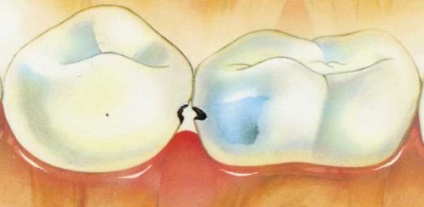

Fogszuvasodás a fogak közötti struktúrát tönkreteszi a zománc, a dentin, és végül fogszövet alátámasztó eszközt. A betegség jellemzője: szuvas kár nehéz diagnosztizálni. Ezért a kezelés az interproximalis fogszuvasodás bonyolult és hosszadalmas folyamat.

A fogszuvasodás a fogak között - kilátás belülről

Kapcsolat zóna érint a fogszuvasodás a fogak között. Függetlenül azonosítani a betegséget nehéz. Győzd válik jelentős, ha a tehermentesítő üreg mérete megnő, a furat eltömődik maradványait ételt a szájába kellemetlen szag. Terápia ennek formája a betegség hosszú és bonyolult. Terápiás intézkedések állnak eltávolításában nagy mennyiségű egészséges szövetek kapcsolat lehetővé teszi a hozzáférést a gyulladásos gócok.

Kapcsolat fogszuvasodás a fogak között

Interdentális szuvasodás formáció gyors terjedését. Ezek a folyamatok kapcsolódó távoli helyeken, amelyek lehetetlen teljesen megtisztítani. Periódusai folyamatosan eltömődött ételmaradékokat. Idővel ezek a bomlás. Teremt ideális környezetet biztosít a létfontosságú tevékenység a kórokozó baktériumok.